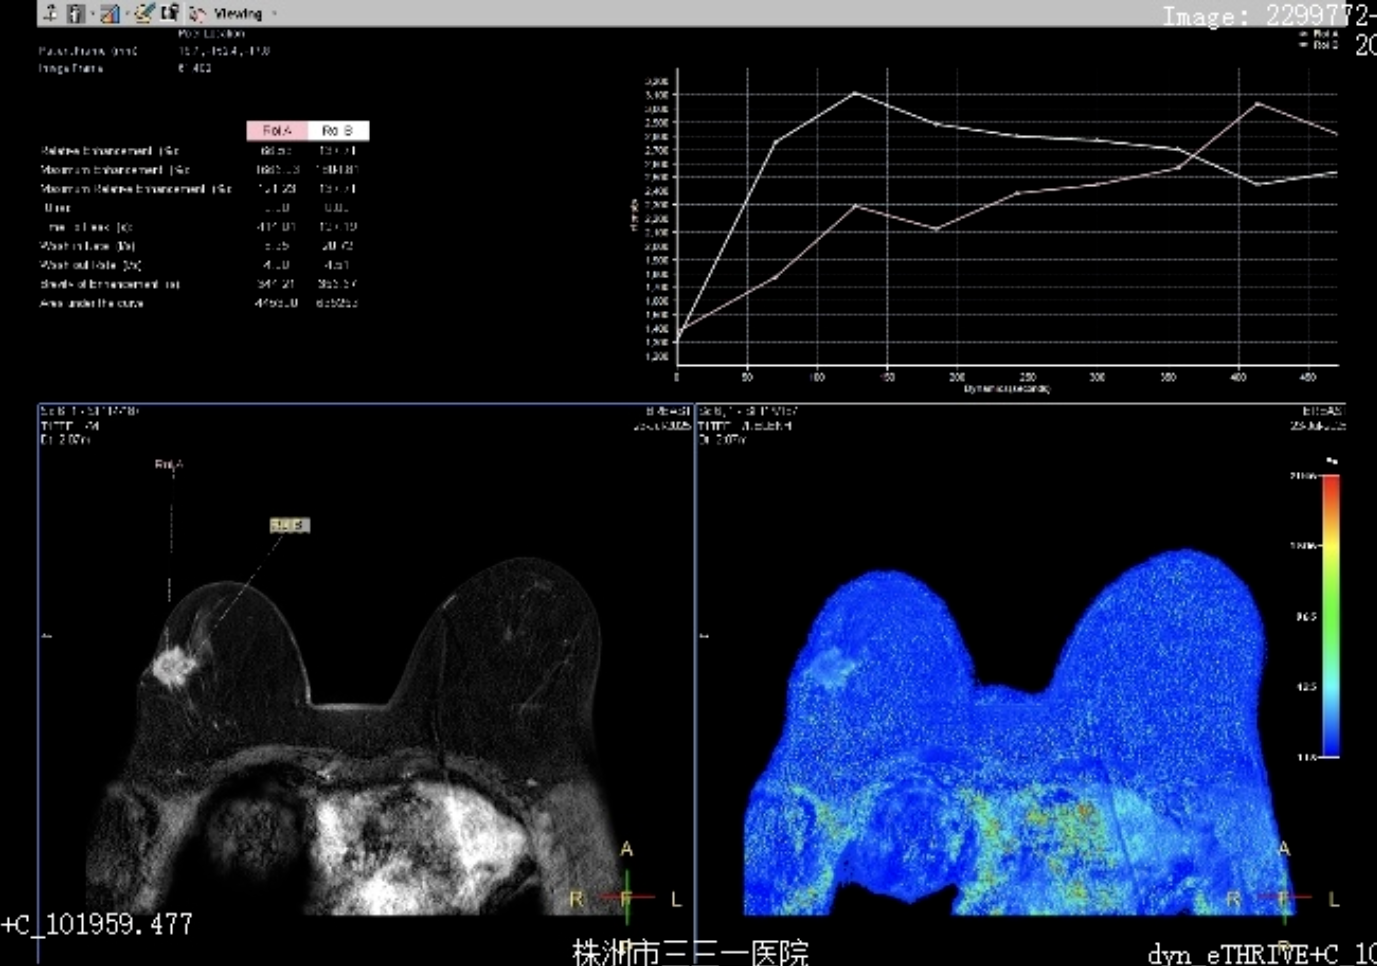

乳腺磁共振增强检查是通过静脉注射造影剂,利用磁共振先进技术清晰显示乳腺组织、病变部位及血供情况的影像学检查,核心价值在于精准评估病灶范围、血供及性质。

通过乳腺磁共振动态对比剂增强成像,能清晰捕捉乳腺组织的血流动力学变化。可帮助对乳腺病变进行定位定性,为乳腺癌早诊早治奠定基础。

在乳腺癌新辅助治疗(术前化疗、靶向治疗)或术后随访中,乳腺磁共振增强可动态监测病灶大小、血供变化及强化模式改变,有助于对化疗反应性的评估,及时调整治疗方案。